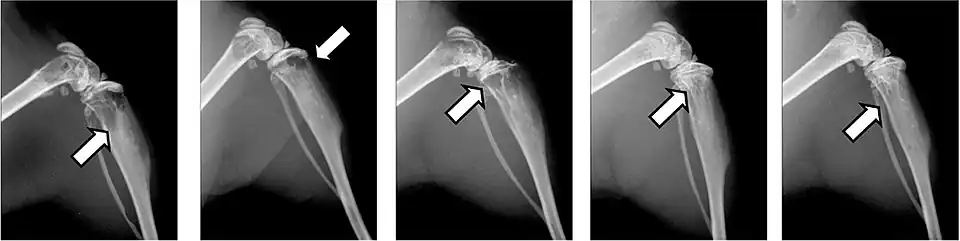

- CT-Aufnahmen einer Hochfrequenzablation (RFA)

-

Vor der RFA: Hinterer oberer Darmbeindorn (Spina iliaca posterior superior) mit osteolytischer Metastase (ca. 2 cm im Durchmesser, siehe Pfeile) -

Während der RFA: A) Die HF-Elektrode wurde direkt in die Knochenmetastase geführt. B) Nach der Ablation wurde eine Mischung aus Knochenzement und Bariumsulfat in den entstandenen Freiraum injiziert. -

Nach der RFA: Die Verteilung des Knochenzementes in dem nach der Ablation entstandenen Hohlraum ist zu erkennen.